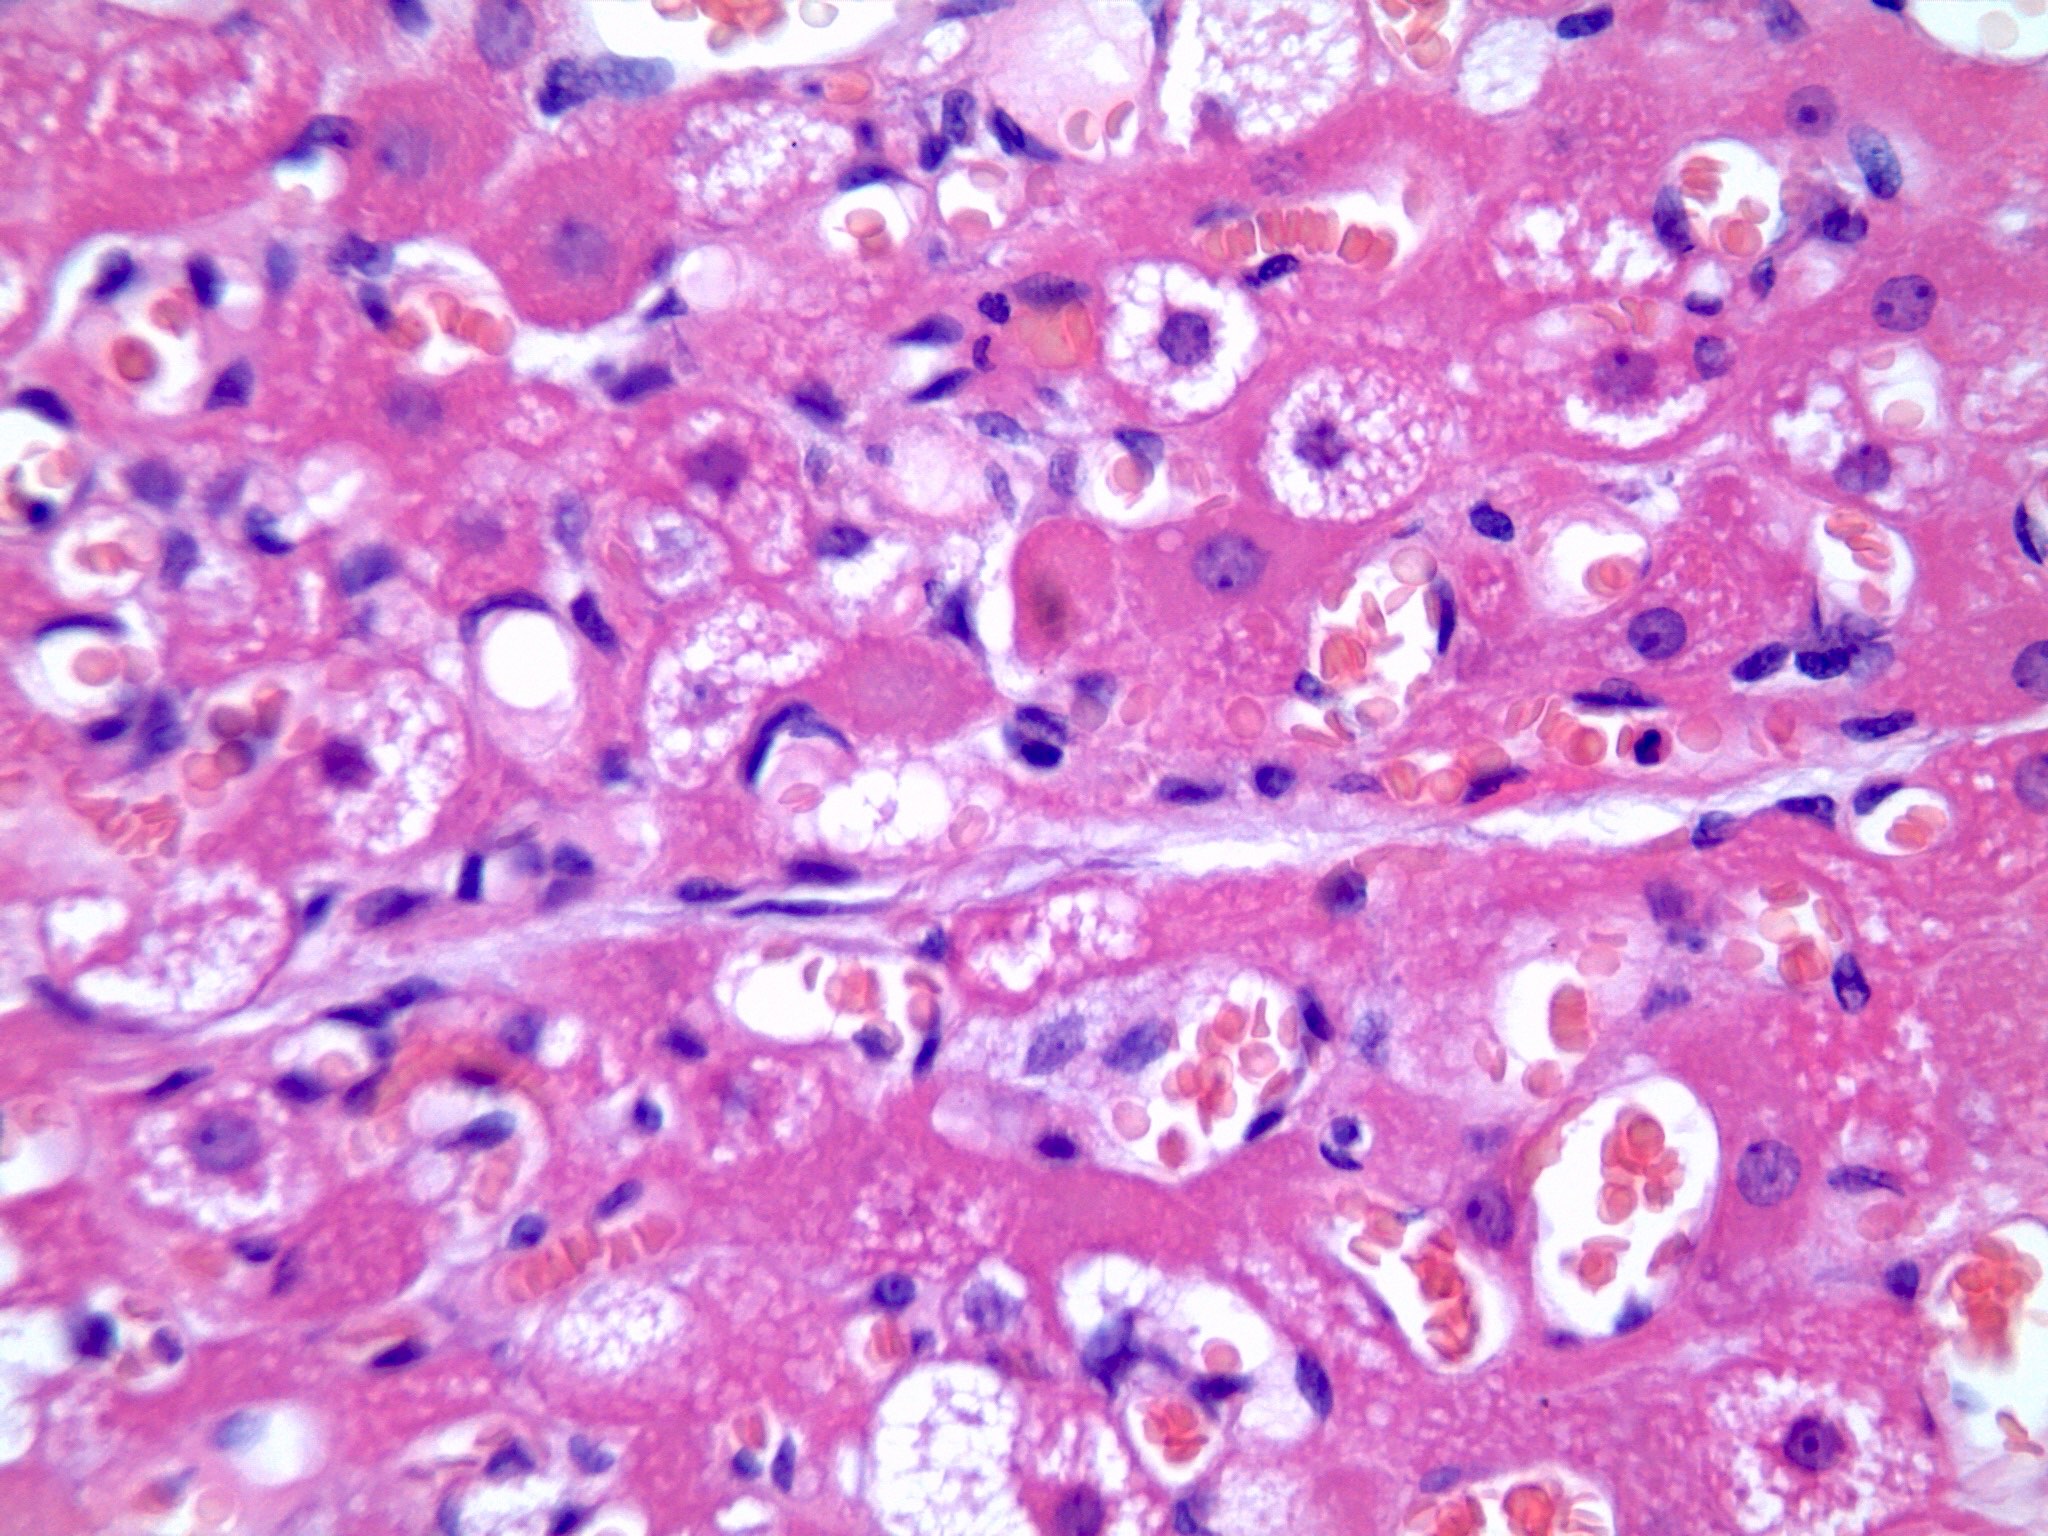

Microscopic (histologic) description

- Neoplastic lesion composed of polygonal brown fat cells with stromal cells in the background (Case Rep Oncol 2017;10:438)

- Large number of pale and eosinophilic brown fat cells with multivacuolated, eosinophilic granular cytoplasm and small central nucleus (about 70%) admixed with variable amount of univacuolated white cells (Case Rep Oncol 2017;10:438, Am J Case Rep 2020;21:e921447, J Comput Assist Tomogr 2019;43:793, J Pathol Transl Med 2017;51:499, Am J Surg Pathol 2018;42:951, Virchows Arch 2021;478:527)

- Multivacuolations resemble lipoblasts

- Morphological variations or subtypes: typical, myxoid (9%), lipoma-like (7%), spindle cell (2%), thick bundles of collagen fibers, presence of mast cells and exclusively containing brown fat cells (Case Rep Oncol 2017;10:438, Am J Case Rep 2020;21:e921447, Virchows Arch 2021;478:527)

- Cytological atypia, necrosis and mitosis is unusual (J Pathol Transl Med 2017;51:499, Am J Surg Pathol 2018;42:951, BMC Surg 2021;21:30)

Microscopic (histologic) images

- Microscopic description: The sections reveal a well circumscribed neoplastic lesion comprising large polygonal cells arranged in sheets. These cells have multivacuolated, granular cytoplasm with small central nucleus admixed with variable amount of univacuolated cells. There is no significant cytological atypia, necrosis or mitosis.